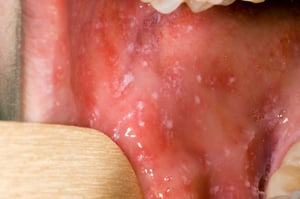

Antes do início da erupção cutânea, podem surgir manchas de Koplik no interior da boca. As manchas de Koplik são pequenas manchas de cor vermelho-vivo com centros brancos ou branco-azulados. Os centros podem se parecer com grãos de areia.

As manchas de Koplik são manchas de cor vermelho-vivo com centros brancos ou azulados que podem se parecer com grãos de areia. Elas podem ocorrer em qualquer parte da boca em pessoas com sarampo.

Imagens por cortesia da Biblioteca de Imagens de Saúde Pública dos Centros de Controle e Prevenção de Doenças.